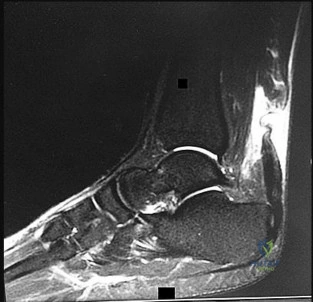

In a minimally invasive or percutaneous repair of a ruptured Achilles tendon, care must be taken to avoid iatrogenic injury to the sural nerve. What is the typical relationship of the sural nerve to the Achilles tendon?

Which of the following is considered the primary and strongest stabilizer against valgus talar tilt within the superficial component of the deltoid ligament of the ankle?

The talus is highly prone to avascular necrosis following displaced fractures of the talar neck. Which artery provides the most significant vascular contribution to the body of the talus?

The artery of the tarsal canal provides the dominant blood supply to the body of the talus. From which main parent vessel does the artery of the tarsal canal directly originate?

From anterior/medial to posterior/lateral, what is the correct anatomical order of structures passing behind the medial malleolus in the tarsal tunnel?

While performing a percutaneous or minimally invasive repair of an acute Achilles tendon rupture, the surgeon must be cautious of the sural nerve. At what approximate distance proximal to the calcaneal insertion does the sural nerve typically cross the lateral border of the Achilles tendon?